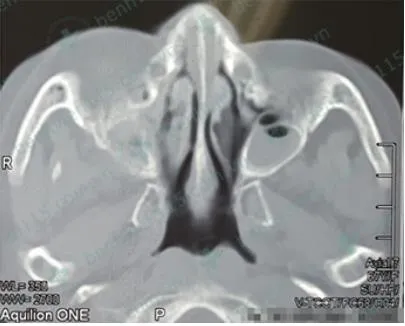

Kết quả chụp CT scan ghi nhận bà N. bị viêm xoang hàm hai bên.  Ảnh: BV CUNG CẤP

Kết quả chụp CT scan cho thấy mờ đặc xoang hàm và sàng hai bên. BS chẩn đoán bà N. bị viêm đa xoang mạn gây biến chứng hốc mắt phải trên bệnh nhân đái tháo đường.